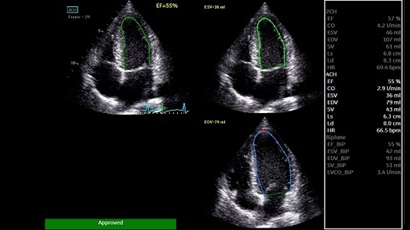

• AUTO 2D EF - режим автоматической недопплеровской количественной оценки глобальной сократительной функции ЛЖ (по Simpson).

• AFI - режим цифровой недопплеровской качественной и количественной оценки региональной сократительной функции ЛЖ.

AUTO 2D EF:

Да

AFI: